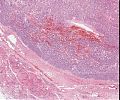

A82 Appendix-Karzinoid

Große, nestartige Verbände neuroendokriner Tumorzellen

A82 Appendix-Karzinoid

Tumorzellnester und diffuse Infiltration der neuroendokrinen Tumorzellen

Appendixkarzinoid

Erkennbar sind isomorphe Tumorzellnester

Appendixkarzinoid

Neuroendokriner Tumor mit nestartigen, trabekulären Formationen isomorpher Tumorzellen